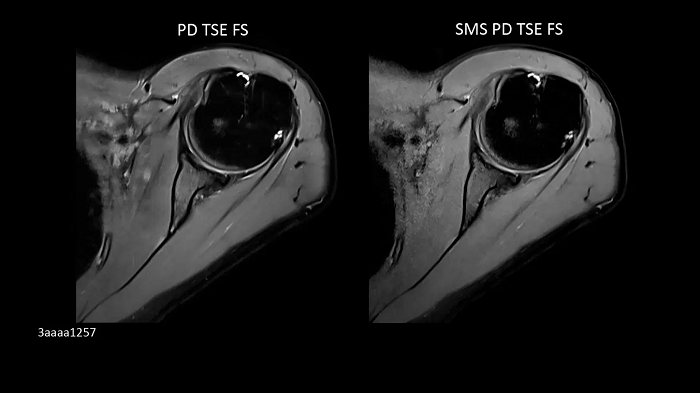

Shoulder imaging

Shoulder Shape 16 coil with patient-adaptive design enables Simultaneous Multi-Slice scan acceleration.

Left:

PD TSE FS | PAT 2 | 0.4 x 0.4 x 3.0 mm3 | TA 4:06 minutes

Right:

SMS PD TSE FS | PAT 2 SMS 2 | 0.4 x 0.4 x 3.0 mm3 | TA 3:08 minutes

Image Credit: Radiologie München Harlaching, Munich, Germany